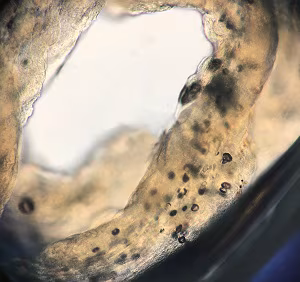

Case #493 – June, 2019

A 36-year-old male returning from a 3-month stay in rural China sought medical attention for a tender, slowly migrating nodule that had developed on his abdomen. The subcutaneous mass was excised in the clinic; a motile, ribbon-like object approximately 5 cm long was found within. The organism was placed into 10% formalin and submitted to the DPDx Team for identification. The gross morphology of the organism is shown in Figures A and B; Figure C shows the internal structure after exposure to lactophenol (100x magnification).

Figure A